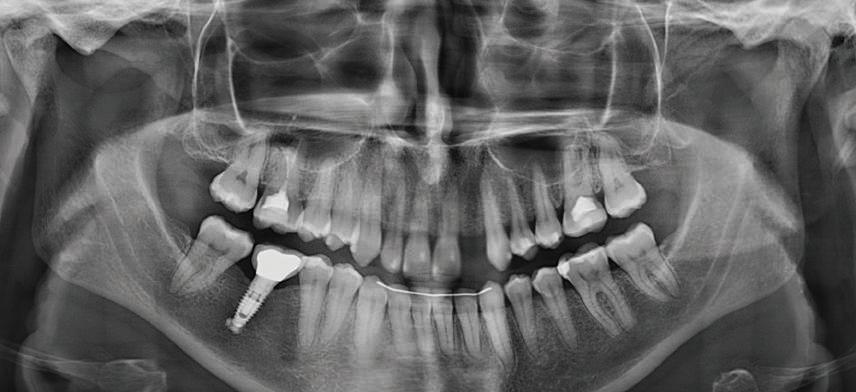

Пациентът постъпи в моята клини ка с наличие на темпоромандибуларен дисфункционален болков синдром, едно странно изместен диск с редукция в дяс ната става, клас II, подклас 2, тесни гор на и долна челюст със струпване, дъл бок овърбайт

орални снимки и снимки на позата, пал пация на мускулите, брукс-чекър, оклу зограми, кондилография, рентгеногра фии, СВСТ и ядрено-магнитен резонанс на темпоромандибуларните стави). Преди началото на ортодонтското лечение всички стари възстановява ния бяха свалени и бяха заменени с дъл госрочни временни от хибридна керами ка. На девитализираните зъби бе прове дено ендодонтско релечение. Индивиду ализиран оклузален сплинт бе направен с цел да се постигне контролирано репо зициониране на долната челюст, като носенето му продължи три месеца до възстановяване на правилната позиция на ставния диск и затихване на орофаци алната болка и дискомфорт в ставата. Брекетите в горната челюст бяха за лепени, за да започне подреждането и нивелирането на зъбите, докато паци ентът все още носеше сплинта. След края на терапията със сплинта бе на правена кондилография, за да се потвър ди триизмерната позиция на долната челюст. След залепване на брекетите в долна

и гингивална усмивка. Започнахме лечението с пълна диагно стика (анамнеза, интраорални, екстра

7Dental Tribune Bulgarian Edition / октомври 2022 г. Преди лечението Фиг. 1 Фиг. 4 Фиг. 7 Фиг. 10 Фиг. 13 Фиг. 16 Фиг. 17 Фиг. 18 Фиг. 19 Фиг. 20 Фиг. 11 Фиг. 14 Фиг. 12 Фиг. 15 Фиг. 8 Фиг. 9 Фиг. 5 Фиг. 6 Фиг. 2 Фиг. 3